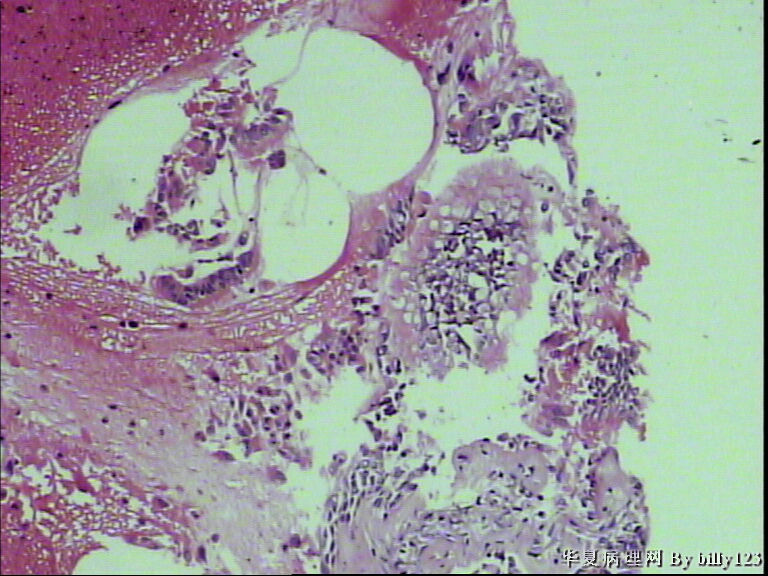

纤支镜活检,女性,75岁,请各位老师指教!

图1